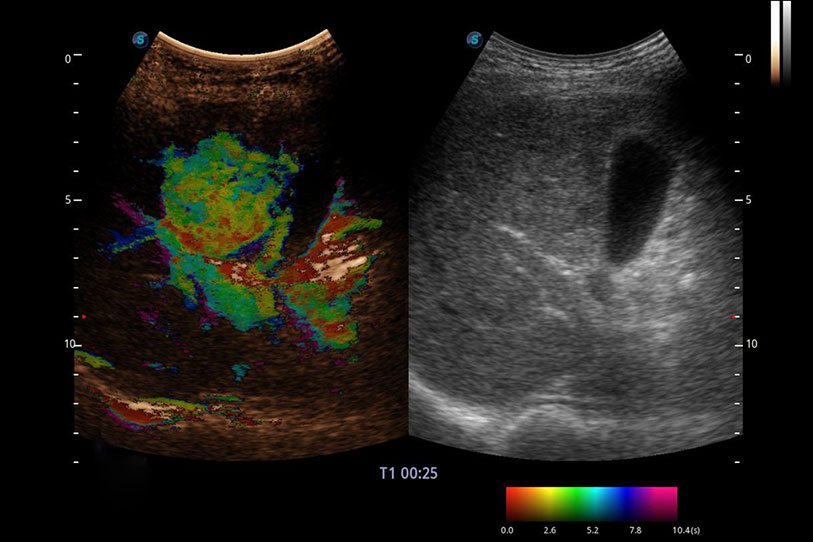

采用紅、橙、黃、綠、青、藍(lán)、紫這七種肉眼最為敏感的色彩,直觀地顯示組織內(nèi)血流灌注的時(shí)間先后信息,更精準(zhǔn)捕捉血流灌注走行細(xì)節(jié)。

操作簡便,無需高頻度外力作用即可真實(shí)反映組織的形變,快速評估腫瘤良惡性。

通過創(chuàng)新的 Matrix E自適應(yīng)濾波器和超長時(shí)間域算法,極大提升超低速微細(xì)血流的檢出能力,同時(shí)更精準(zhǔn)地濾除軟組織和噪聲信號,為獸用醫(yī)生提供以往無法通過常規(guī)血流獲得的疾病診斷信息。